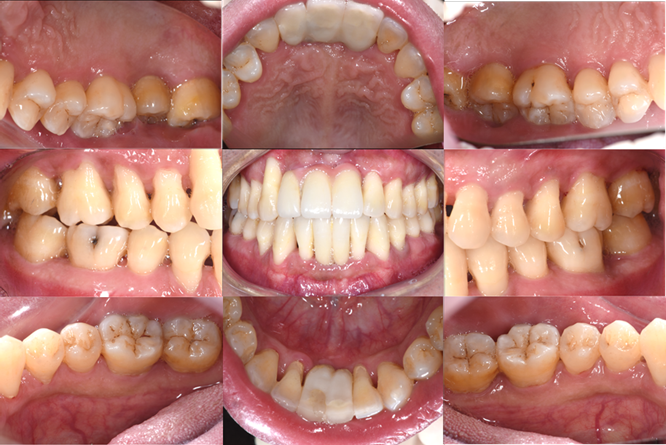

▲牙周治疗+种植治疗后口内彩幻